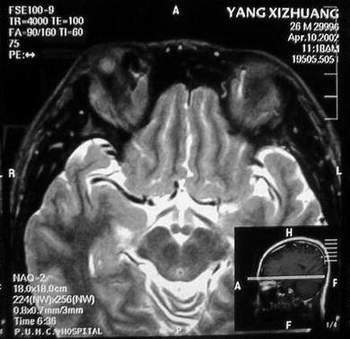

MRI及增强结果如下:

患者压颈及其它Valsava试验结果阴性。从MRI分析,在T1、T2、T+C检查该支血管均为明显流空现象,说明该血管血流速度很快,而从走行和分布看,眼上静脉可能性很大。也许也不能除外异常的眼动脉或异常血管。眶内主要可能的血管病变包括颈内动脉海绵窦瘘(高流窦)、AVM、眼眶静脉曲张、海绵状血管瘤、静脉性血管瘤、毛细血管瘤和眶内动脉瘤。。 1、颈内动脉海绵窦瘘:该患者临床有一部分支持该诊断。但从影像分析,海绵窦未见明显扩张;眼外肌未见明显充血扩张的长T1、长T2信号;颈内动脉海绵窦瘘常可见继发到血栓,可见到短T1、长T2的血栓信号。 2、眼眶静脉曲张:该疾患一般常见于小儿。该患大多数会出现Valsava试验阳性,间歇性突眼。不符合该患。影像学检查,于曲张静脉内常可见血栓和静脉石。所以不符合该患。 3、AVM:患者目前的影像学资料尚不全面,但可符合该诊断。临床上改病常见于30岁左右年轻人,单侧发病,于本患较符合。问题在于临床没有明确的血管杂音,似乎难以解释。 4、该患影像学与海绵状血管瘤差别很大,所以可基本排除此诊断。 5、静脉性血管瘤和毛细血管瘤:MRI中等T1、长T2信号,较易与本病鉴别。 6、眶内动脉瘤:我觉得患者并不能排除本病,但同样,由于波动性阴性,似乎也难以解释。 纵上所述:本人觉得,患者AVM可能性较大,同时不能除外眶内动脉瘤。 关于进一步检查,我觉得DSA价格过于昂贵。是否可先进行彩色多普勒检查,首先可以明确是静脉系统还是动静脉瘘抑或是动脉瘤。第二步,可进行MRA检查,可以清楚地显示海绵窦地相关关系,并可借此诊断或排除颈内动脉海绵窦瘘。如还需第三部检查,可进行MRV检查,对静脉系统进一步评价。三种检查总共的费用2000多圆,但给予我们的信息量已经很丰富了。 敬请各位医师提出自己的见解。 谢谢!

根据MRI显示眼上静脉扩张可能性很大。眼上静脉扩张有几种原因:1.颈内动脉海绵窦瘘,2.眶尖肿瘤,3.甲亢,4.炎性假瘤.病人球结膜充血示静脉回流障碍,动脉瘤可能性小.根据病史,我认为排除1,2.则考虑3,4.查T3,T4.激素作诊断性治疗.